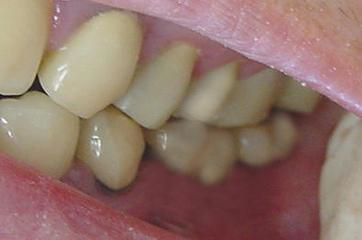

Figuras 16. Mostra o caso pronto, com as duas coroas provisórias em posição.

Importante salientar que após a cicatrização final, osseointegração, as coroas da região serão refeitas, para se atingir mais estética e equilíbrio na oclusão do paciente.